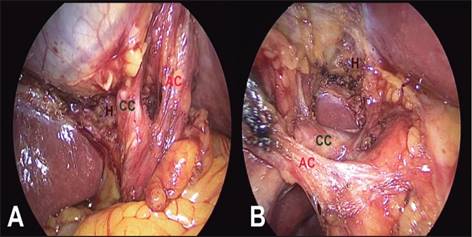

1. Establecer la identificación de la visión crítica de seguridad: La visión crítica de seguridad puede ser comprobada usando una doble visión, anterior y posterior, de las estructuras (figura 3).

Fuente: Chama, Farell RJ, Cuevas VJ. 2021

Figura 3. Visión crítica de seguridad de Strasberg

La visión crítica de seguridad se debe comprobar desde la visión directa en planos contrarios en A: derecha a izquierda y en B: izquierda a derecha. Las letras señalan H: Lecho hepático, AC: Arteria cística y CC: Conducto cístico.(15)